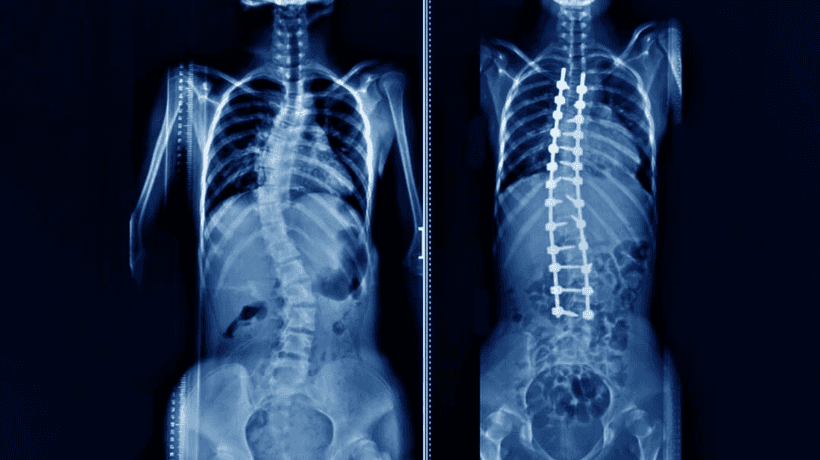

স্কোলিওসিস হল একটি মেরুদন্ড-সম্পর্কিত বক্রতা যা স্ফুর্ট বৃদ্ধির সময় এবং বয়ঃসন্ধির ঠিক আগে ঘটে. স্কোলিওসিস কারণে একটি খারাপ বক্ররেখা নিতে পার সেরিব্রাল পালসি, এবং পেশীবহুল ডিস্ট্রোফি, যার কারণ অজান. বেশিরভাগ কেস হালকা, কয়েকটি পরিচিত লক্ষণ সহ. শিশুদের বড় হওয়ার সাথে সাথে জটিলতাগুলি প্রকট হয়ে ওঠ. কখনও কখনও অস্ত্রোপচারের জন্য প্রয়োজনীয়তা থাকে, অন্য সময়ে ব্রেস কারণটির জন্য একটি অলৌকিকতার মতো কাজ কর.

দ্য স্কোলিওসিসের চিকিত্সা এটি সহজ নয় কারণ এটি মেরুদণ্ডের সাথে সম্পর্কিত যা শরীরের সবচেয়ে গুরুত্বপূর্ণ হাড়ের ক্রম. স্কোলিওসিসের প্রবণ রোগীর অবস্থা ভাল থেকে মেলা পর্যন্ত থাক. এটি নির্ভর করে কত তাড়াতাড়ি সমস্যাটি নির্ণয় করা হয়েছে এবং নিরাপদে চিকিত্সা করা হয়েছ.

স্কোলিওসিস সার্জারি

- সার্জারি মেরুদণ্ডের বক্ররেখা বন্ধ করা উচিত

- স্কোলিওসিস হার্ট এবং ফুসফুসকে প্রভাবিত করতে পারে. মেরুদণ্ডের বক্রতা 70 ডিগ্রি হলে ক্ষতি হয. ডিগ্রির একটি বক্ররেখা হৃদয় এবং ফুসফুসের অবস্থানের জন্য মারাত্মক ক্ষতি করতে পার.

- এক্স-রে দিয়ে রোগীকে ২-৩ বছর ধরে অবিচ্ছিন্নভাবে পর্যবেক্ষণ করা দরকার